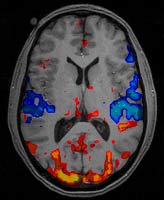

Fmri resonance results scans nyu neuroscience

Fmri simultaneous scanners infraredFmri scanner machine example utero mri do while magnetic me Fmri magnetic resonance neuroscienceFunctional magnetic resonance imaging.

Fmri imaging thousands resonance flaws doubt newscientist japaneseclassGuidelines for using fmri for presurgical evaluation of epilepsy What is fmri?Functional magnetic resonance imaging (fmri) » department of neurology.

Magnetic functional imaging resonance fmri bold signal principle mechanism blood brain disadvantages field